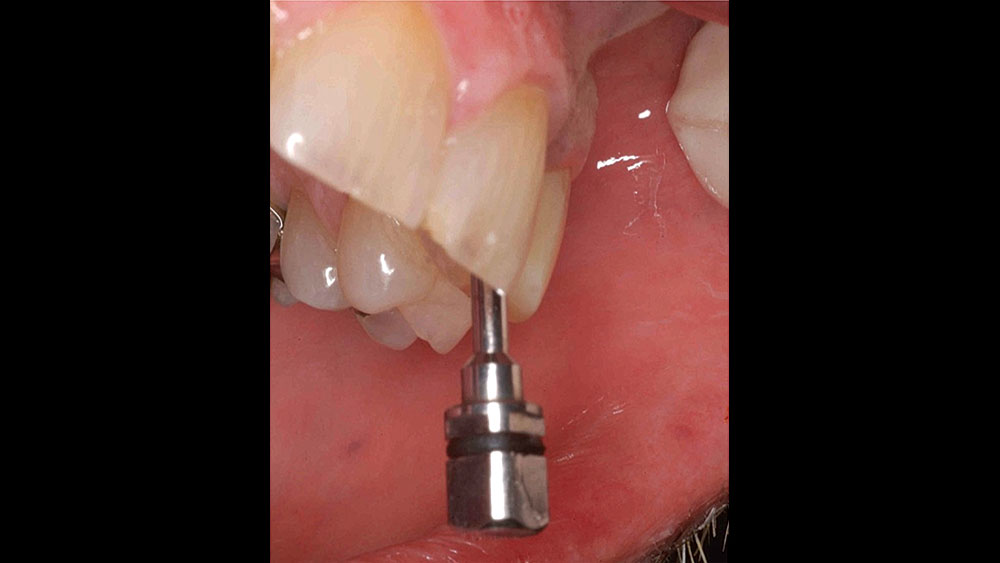

To achieve an optimal functional and esthetic outcome, the implant must be placed correctly with regard to trajectory, adjacent vital anatomy, and buccolingual, apicocoronal and mesial-distal positioning. Situating the implant so that the edges of the osteotomy are at least 2 mm from the buccal and lingual cortical plates, 2 mm from adjacent roots, 2 mm from vital structures, and 2–3 mm below the crest of tissue will keep the implant within the envelope of acceptability. The implant trajectory should emerge lingual to the incisal edge of the planned restoration, which allows for a screw-retained crown.

• Angulation lingual to the incisal edge

This case is an example of an ideal clinical situation for dentists who are new to placing implants in the esthetic zone. The patient requested treatment for a fractured upper lateral incisor. After extraction, grafting and healing, ample bone and soft tissue were present, and an implant was placed in optimal position for an esthetic result. The screw-retained restoration predictably restored form and function, illustrating the beautiful results that can be achieved by observing simple surgical and prosthetic guidelines.